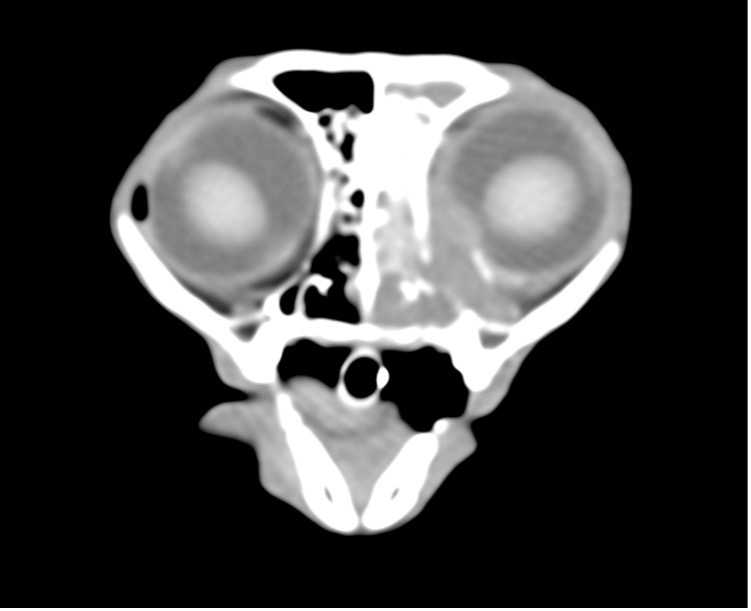

鼻腔リンパ腫の猫の1例

はじめに 鼻腔リンパ腫は猫の鼻腔内腫瘍の中で最も多く約70%を占め、またリンパ腫の次に多いのは腺癌である。症状は片側性の鼻汁、鼻出血が最も多くその他顔面変形、眼球の突出、鼻閉音、努力呼吸、食欲不振などが認められる。治…